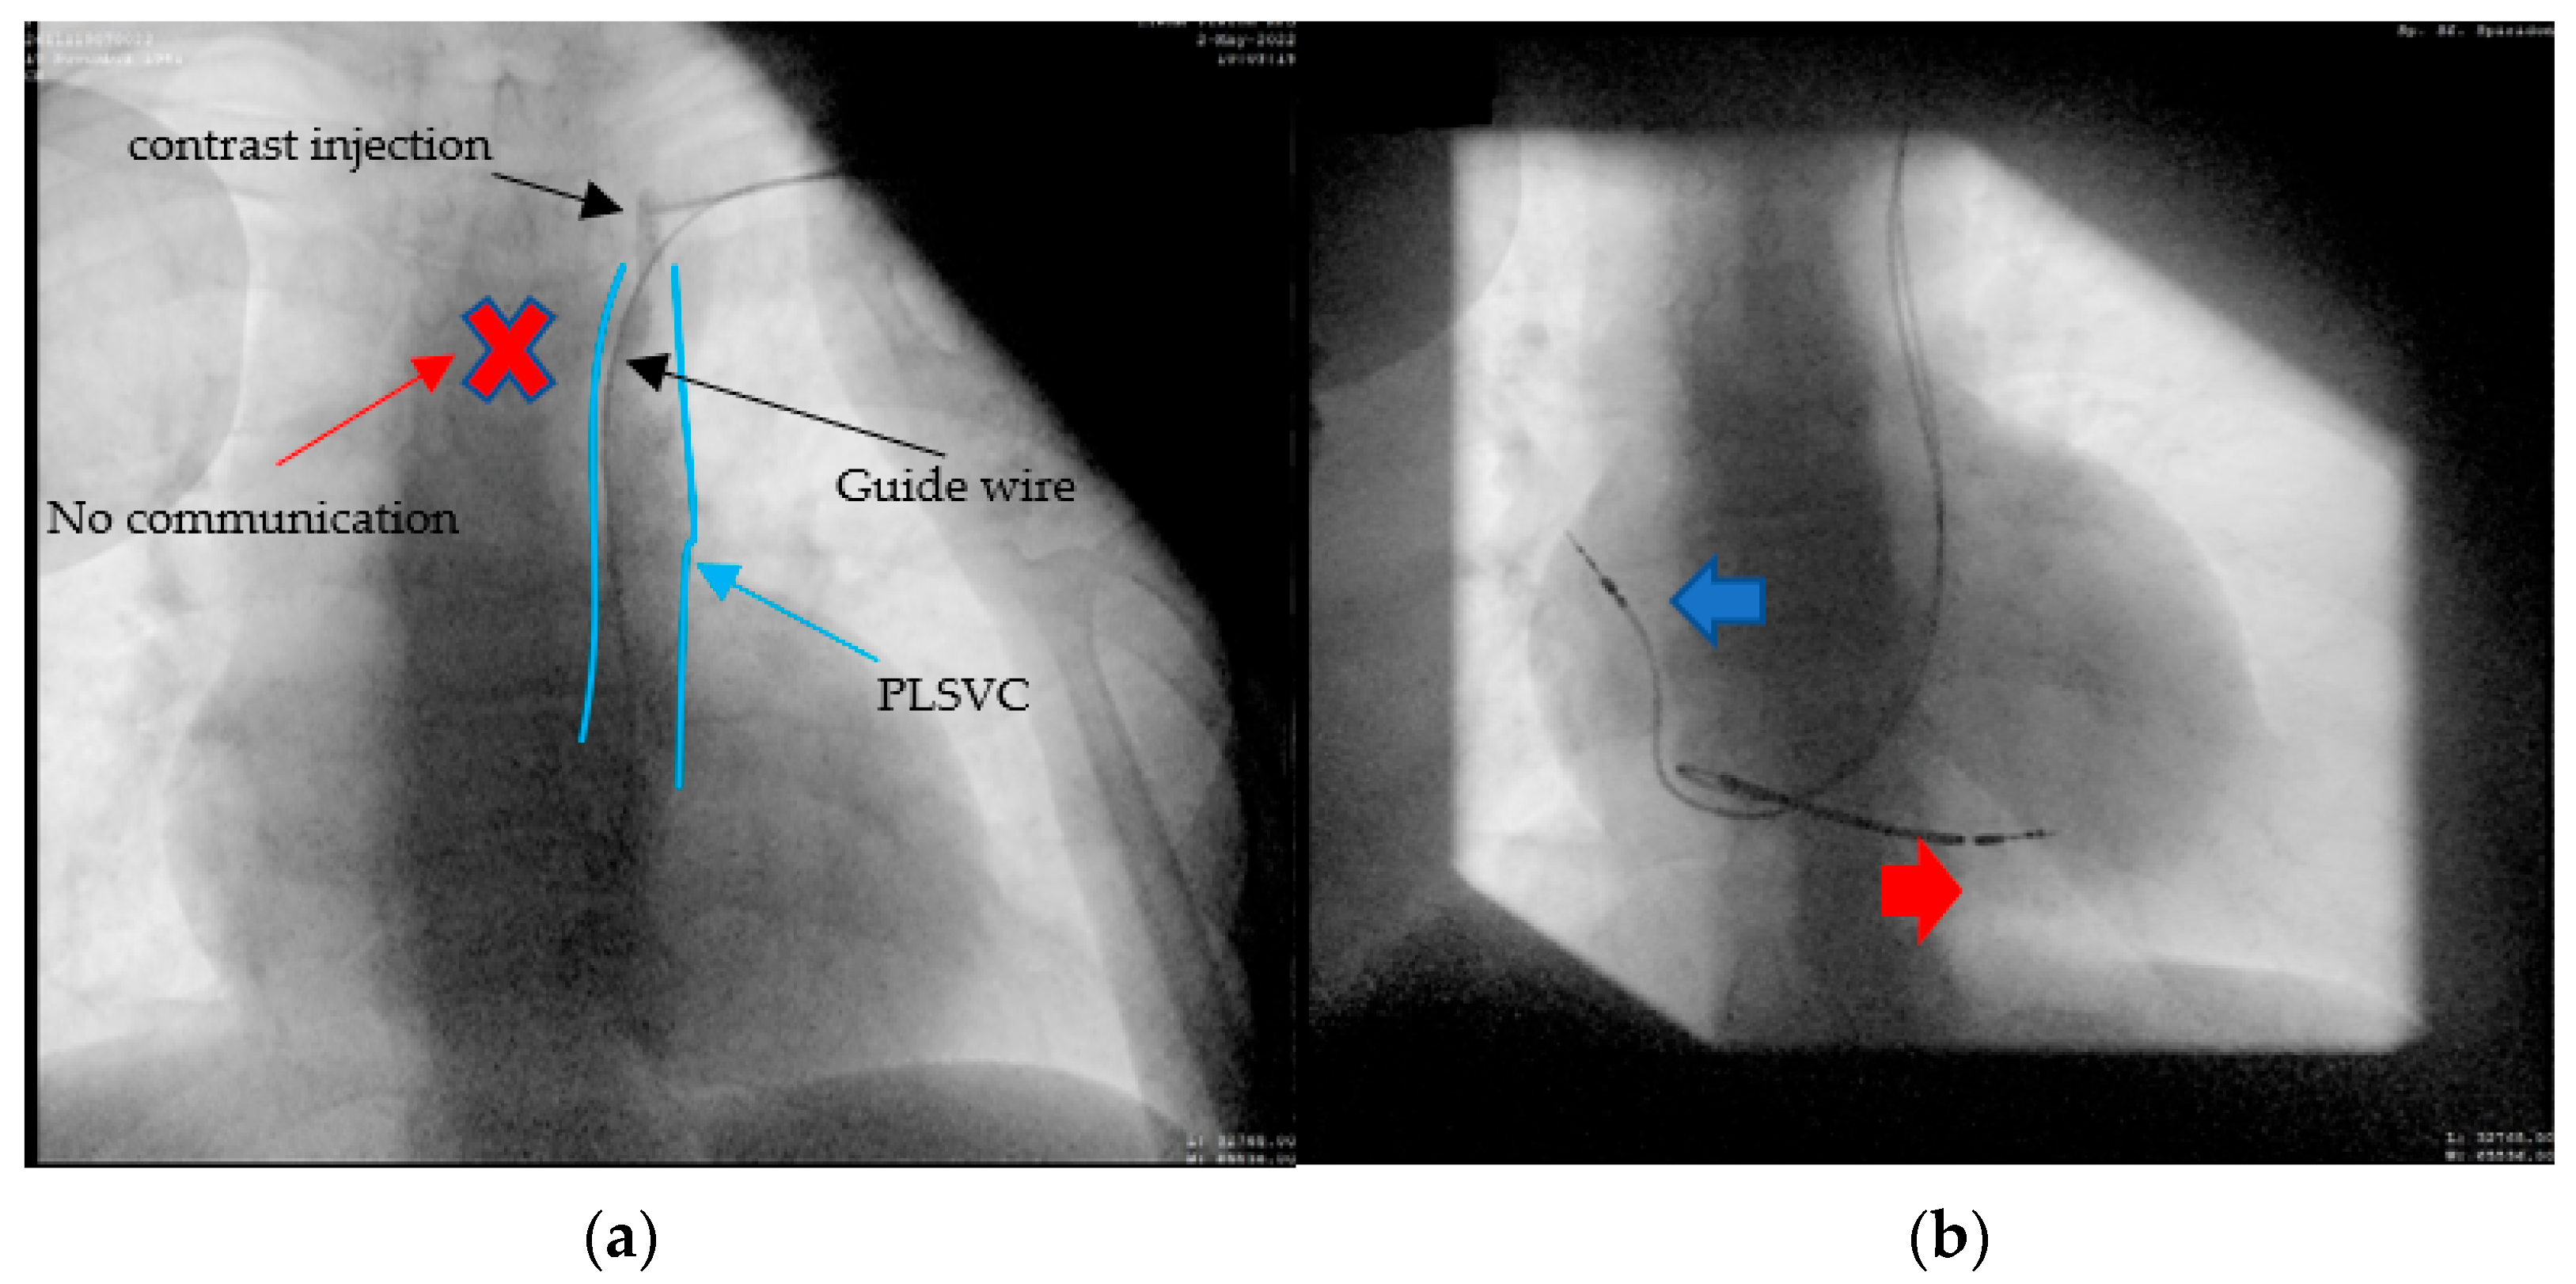

2.1. Case 1. (Type IIIB)